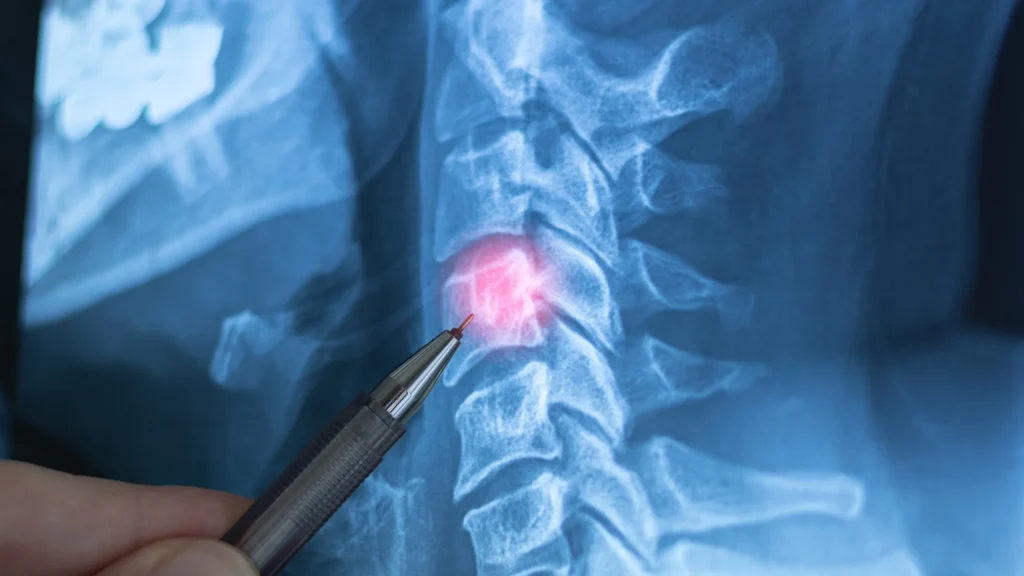

Learn how to place points on cervical flexion and extension views for proper AOMSI determination.

Dr. Steven Kraus, DC, FIACN, DIBCN, CICE, FASA, FICC and Certified Independent Examiner for Impairment Ratings will demonstrate how to accurately place points on the radiograph views to obtain AOMSI measurements from cervical spine flexion and extension radiographs in accordance with the AMA Guides To The Evaluation of Permanent Impairment using both the 5th and 6th Editions.